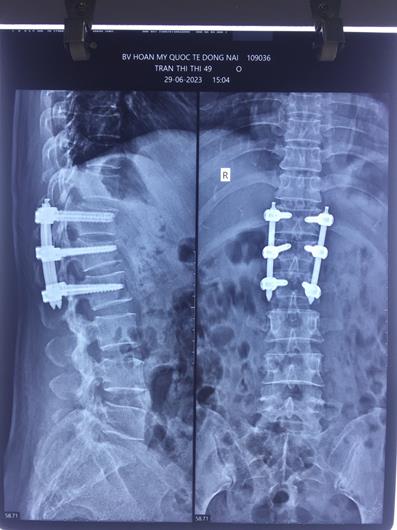

Phim chụp cột sống của bệnh nhân trước và sau khi được phẫu thuật

Thời điểm nhập viện, bà T. đau lưng rất nhiều, chỉ nằm im một chỗ, không thể xoay trở người. Kết quả thăm khám, chụp phim, bác sĩ chẩn đoán bà T. bị gãy vỡ thân đốt sống L1, cần phải can thiệp mổ cấp cứu để làm cứng, cố định đốt xương sống bị gãy, giúp vết thương chóng lành, có thể đi lại được và ngăn ngừa các biến chứng do nằm lâu, yếu liệt, gù vẹo cột sống.

BS CKI. Trần Minh Thành, Khoa Ngoại chấn thương chỉnh hình, phục hồi chức năng cho biết, trong khoảng 1 giờ đồng hồ, các bác sĩ đã tiến hành phẫu thuật làm cứng cố định cột sống bằng phương pháp xâm lấn tối thiểu. Đây là phương pháp hiện đại, rút ngắn thời gian phẫu thuật, mất ít máu trong mổ, hạn chế nhiều rủi ro và giúp bệnh nhân phục hồi nhanh chóng.